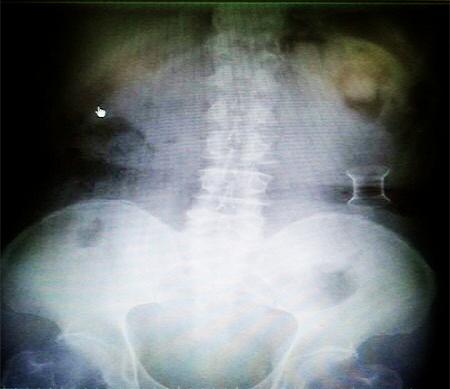

受試患者在結(jié)腸端端吻合術(shù)中,使用我司新研制產(chǎn)品達(dá)到了理想的預(yù)期效果。患者術(shù)后7天、14天X光片顯影,可降解腸道支架均能按研制設(shè)計(jì)的預(yù)期時(shí)間節(jié)點(diǎn)保持應(yīng)有強(qiáng)度,術(shù)后21天X光片顯示可降解腸道支架已完全破碎,并排出體外。在整個(gè)試驗(yàn)過程中,病患無(wú)任何不良反映,耐受良好。